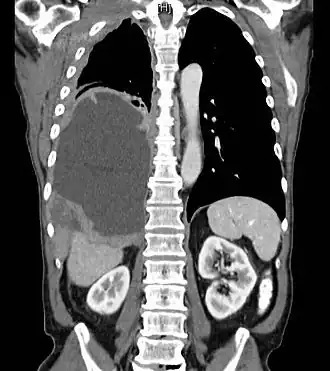

Tomodensitométrie thoracique montrant un mésothéliome dans le poumon droit (à gauche dans l'image).